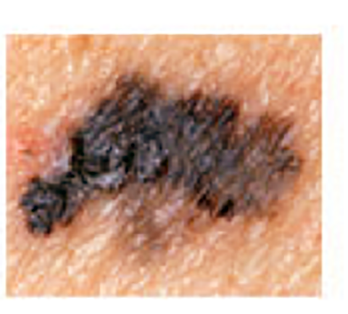

Melanoma Photos

Amelanotic melanomas may be pinkish-looking, reddish, purple, normal skin color or essentially clear and colorless.